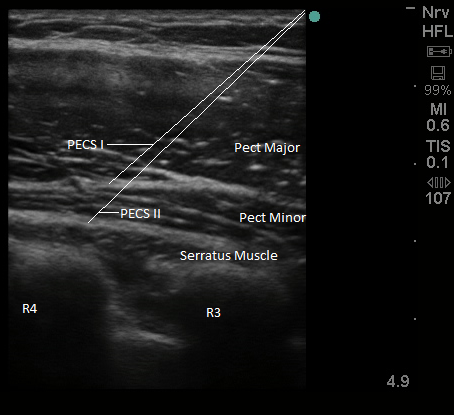

Figure 2. Sonoanatomy and needle tip placement for PECS I/II

For the PECS I block, after image optimization, the needle is inserted medial to lateral in an oblique manner until the tip enters the plane between the pectoralis major and minor muscles between the 3rd and 4th ribs, and 10 ml of local anesthetic is injected under ultrasound guidance while visualizing the spread of local anesthetic in the plane between the muscle layers.

For the PECS II block, the needle is then advanced into the plane between the pectoralis minor and serratus muscles, and 20 ml of local anesthetic is injected watching for spread between the muscle layers under ultrasound guidance.